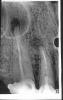

miv Опубликовано 26 октября, 2006 Автор Поделиться Опубликовано 26 октября, 2006 Есть много,друг Горацио.на свете,что и не снилось нашим мудрецам Классика...Ждём снимки(и не только клыка) Добрый вечер,только,что от врача,снимок прилагаю,на словах было сказано зуб абсолютно точно стоит в гайморовой пазухе,будем перепломбировывать(правда не знаю чем,если говорилосьчто для моего зуба такой длиннны инструмент еще не изобрели), будем ставить лекарство,прочитав Ваши ответы ,спросила какое лекарство,гидроокись кальция?В ответ лекарст разныхмного,не только гидроокись кальция.Вобщем,жду вашего приговора, что может быть,если действительно зуб в гайморовой,и как сказала врач результат может быть еще хуже,чем сейчас. Ссылка на комментарий

Dr. Smile Опубликовано 26 октября, 2006 Поделиться Опубликовано 26 октября, 2006 Добрый вечер,только,что от врача,снимок прилагаю,на словах было сказано зуб абсолютно точно стоит в гайморовой пазухе,будем перепломбировывать(правда не знаю чем,если говорилосьчто для моего зуба такой длиннны инструмент еще не изобрели), будем ставить лекарство,прочитав Ваши ответы ,спросила какое лекарство,гидроокись кальция?В ответ лекарст разныхмного,не только гидроокись кальция.Вобщем,жду вашего приговора, что может быть,если действительно зуб в гайморовой,и как сказала врач результат может быть еще хуже,чем сейчас. По снимку, зуб НЕ в гайморовой. Ссылка на комментарий

annda Опубликовано 26 октября, 2006 Поделиться Опубликовано 26 октября, 2006 Добрый вечер,только,что от врача,снимок прилагаю,на словах было сказано зуб абсолютно точно стоит в гайморовой пазухе,будем перепломбировывать(правда не знаю чем,если говорилосьчто для моего зуба такой длиннны инструмент еще не изобрели), будем ставить лекарство,прочитав Ваши ответы ,спросила какое лекарство,гидроокись кальция?В ответ лекарст разныхмного,не только гидроокись кальция.Вобщем,жду вашего приговора, что может быть,если действительно зуб в гайморовой,и как сказала врач результат может быть еще хуже,чем сейчас. По снимку,оба перелечивать.Хотелось бы на другие посмотреть. Ссылка на комментарий

annda Опубликовано 27 октября, 2006 Поделиться Опубликовано 27 октября, 2006 тгене,что все это время будет с коронками,они сейчас держатся только за счет бюгеля не знаю и, что значит сейчас много лекарст, которые вводятся в канал.Я вообще-то астматик и аллергик,правда вроде на лекарства ничего не было,но все же, еще ее фразы,вы склонны к кистообразованию видимо и возможно вы так среагировали на раствор чем мы промываем каналы, и все-таки зуб в гайморовой или нет и есть ли киста. Вы узнали конкретно,что это за раствор?Узнайте,скажите ,буду делать аллергопробы(а они вам и реально не помешают). Чисто моё мнение высказываю. На раствор ТАК зубы среагировать не могли.Они так могли среагировать только на недостаточную механическую и химическую(эти самые растворы для промывания) обработку канала и недостаточную обтурацию(пломбировку)канала. На снимке(вашем) недостаточная обработка выражается в малой конусности канала(каналы узенькие,одногодиаметра на всём протяжении),недостаточной длине обработки(в клыке,конкретно).Качество обработки зависит от инструментов,которые применчет врач,и техники обработки,которую применяет тот же врач.Про растворы на снимке не видно,ничего не скажу.Скажу только,что мыть надо долго,не менее 30мин канал(включая время непосредственной обработки инструментами)Пломбирование сами видите. Кист нет,есть деструкции(дефекты)костной ткани вокруг корней,небольшие,скорее всего с грануляциями. Настоящие кисты-это полости,выстланные эпителием и заполненные жидкостью.Как правило,на снимке гораздо бОльших размеров,с чёткими границами.Если бы корень с такой патологией на снимке выстоял в вашу гайморову,гайморит УЖЕ замучил бы вас.Интересно,что там замазали на картинке справа?Интересно было бы увидеть другой клык. ПО сабжу-можете потерять и деньги,и оставшиеся зубы,и нервы.Придётся платить за имплантаты.Готовы к подвигам? Ссылка на комментарий